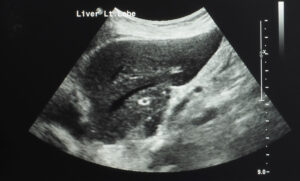

La elastografía por ultrasonido funciona utilizando ondas sonoras para medir cuán rígido o elástico es el tejido hepático. Durante el examen, el dispositivo de ultrasonido envía pulsos suaves a través del hígado. Estos pulsos crean ondas de cizallamiento que viajan por el tejido, y se mide la velocidad a la que se desplazan. Un tejido hepático más rígido permite que las ondas viajen más rápido, lo que puede indicar fibrosis u otras anormalidades. Los resultados se traducen luego en datos cuantitativos que los médicos pueden usar para evaluar la salud del hígado y guiar decisiones de tratamiento.